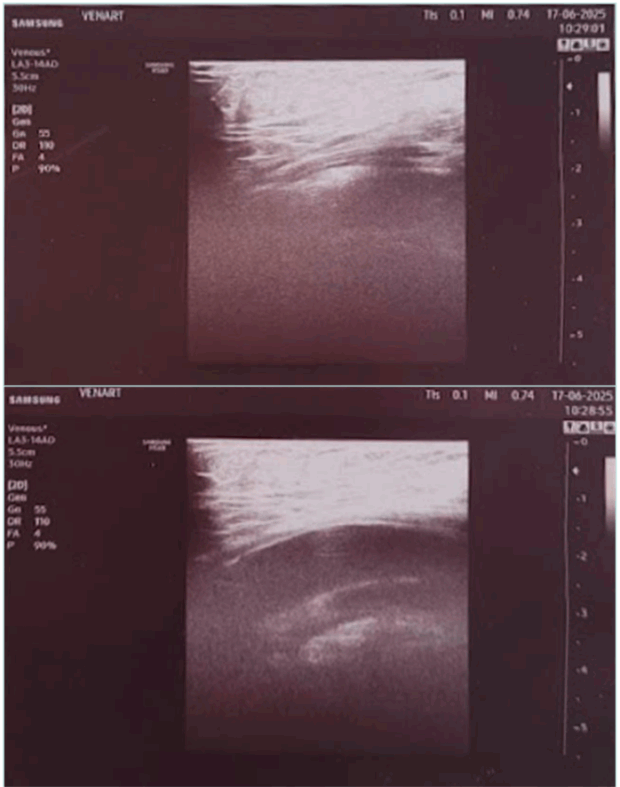

If there is no superficial venous insufficiency associated, in a supine patient, US can appear as normal (Figure 2).

Figure 2. Obese patient with normal non-dynamic venous duplex ultrasound and popliteal venous compression.

When symptoms of venous insufficiency are documented, dynamic tests must be added to confirm or eliminate the diagnosis of popliteal vein compression.

In the tiptoe test, the patient is standing, preferably on a phlebologic stool, with only the anterior part of his feet on the edge. The US probe is placed longitudinally on the popliteal fossa to identify the popliteal vein. The patient is asked to slowly move up and down: compression of the vein by muscular structures of the sural triceps is confirmed by flow restriction in color or power Doppler mode. We consider that clinically significant compression implies a positive test in both extension and flexion of the foot (Figure 3).

Figure 3. Ultrasound image from the tiptoe test. (Upper image) foot extended. (Lower image) foot in neutral position.